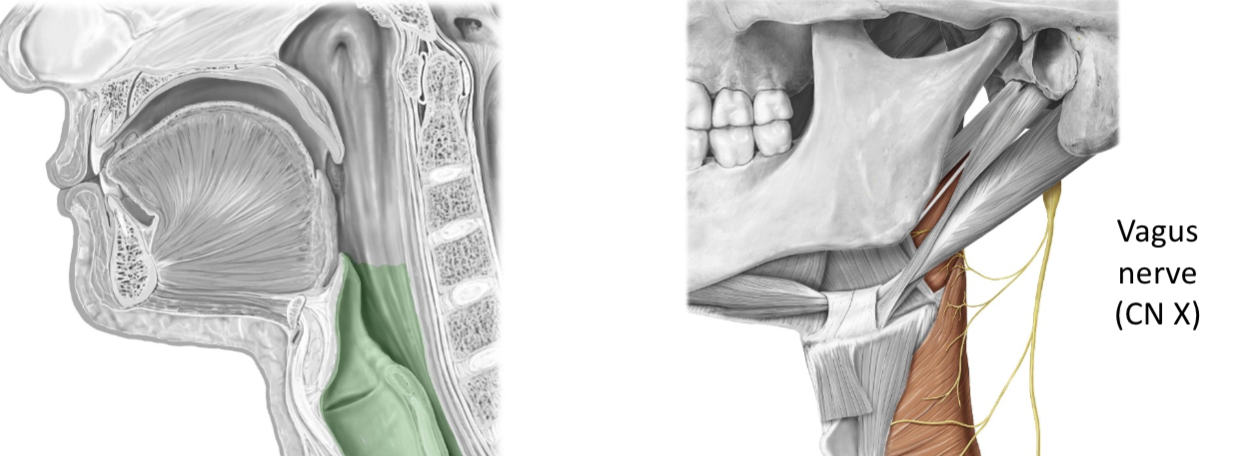

CN X – Vagus Nerve

SPECIAL SENSORY: Taste from epiglottis and pharynx

GENERAL SENSORY: From pharynx and larynx

GENERAL MOTOR: Most pharynx muscles, most soft palate muscles and all larynx muscles

VISCERAL MOTOR (Parasympathetic): Smooth muscle of most of the GI tract, cardiac muscle, and glands in lungs, pharynx, larynx, trachea, and most abdominal organs

CN XI – Spinal Accessory Nerve

GENERAL MOTOR:

Trapezius and Sternocleidomastoid muscle